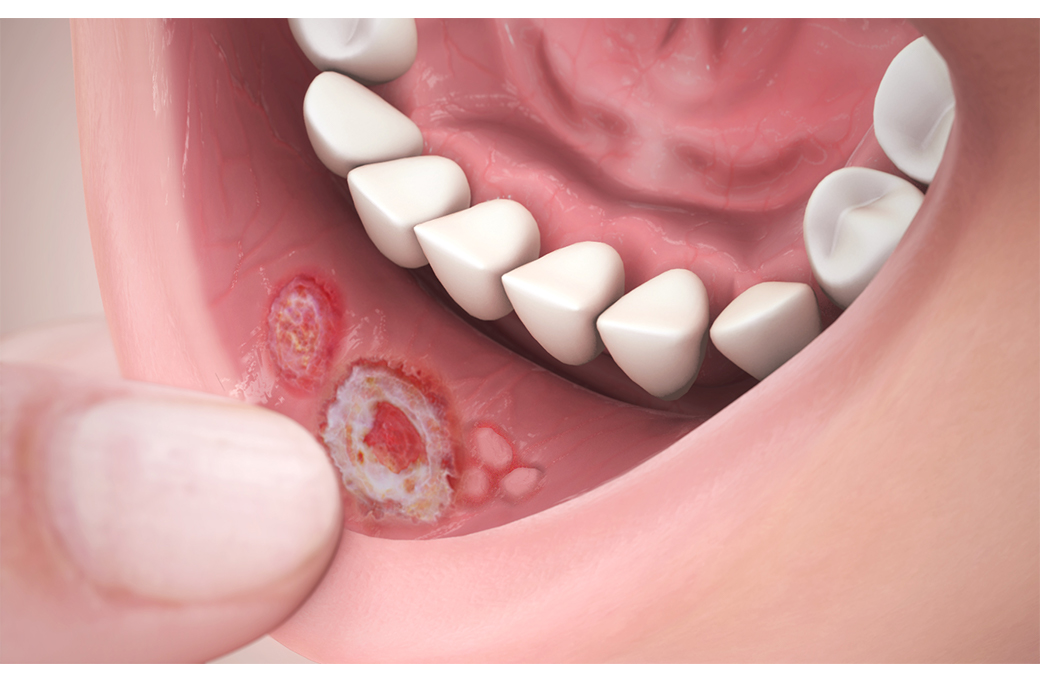

구내염이란 원인균이 알려진 감염에 의하거나 또는 비감염성 원인에 의해 입 안 점막(치아 주위 잇몸, 볼이나 입술 안쪽 점막, 입천정의 구개점막, 혀와 주변 점막)에 염증이 생기는 질환을 말합니다. 원인 요소를 기준으로 세균 감염, 바이러스 감염이 원인인 단순포진(헤르페스 구내염), 진균(곰팡이균)감염이 원인인 구강 캔디다증 등의 감염성 구강점막 질환과 자가면역이나 알레르기 반응에 인한 것으로 알려진 재발성 아프타성 구내궤양, 편평태선, 유천포창, 천포창 등의 비감염성 구강점막 질환으로 나눌 수 있습니다.

구강점막은 신체의 외부와 내부를 연결하는 위치에 있어 신체의 내부적 변화와 외부적 자극으로부터 모두 영향을 받고, 전반적인 건강 상태를 반영하기 때문에 혀와 구강점막의 건강상태가 전신 건강의 거울이라고도 합니다. 구강점막에 나타나는 여러 질환 및 구내염의 원인을 정확하게 알 수는 없지만, 스트레스, 피로, 호르몬 변화, 생리주기, 갑작스러운 체중 변화, 비타민 B12 결핍, 철분과 엽산 결핍, 면역력 저하 등이 발병에 영향을 미치는 것으로 알려져 있습니다. 이 외에도 볼을 씹거나, 음식이나 알레르기, 치약 성분 등으로 인해 구강점막 질환이 발생할 수 있습니다.

각 질환의 원인에 따라 항바이러스제, 항진균제, 항생제, 부신피질호르몬제, 면역억제제 등의 약물치료와 함께 구강위생 및 영양개선, 스트레스 경감 등 보조적인 요법을 적용합니다. 최근에는 레이저도 구강점막질환 치료에 많이 활용됩니다.

재발성 아프타성 구내궤양

대게 1~2주 이내에 자연적으로 치유되며, 연고제나 항균세정제를 사용하면 일시적으로 도움이 됩니다. 심한 경우에는 스테로이드 제제를 사용하기도 합니다.